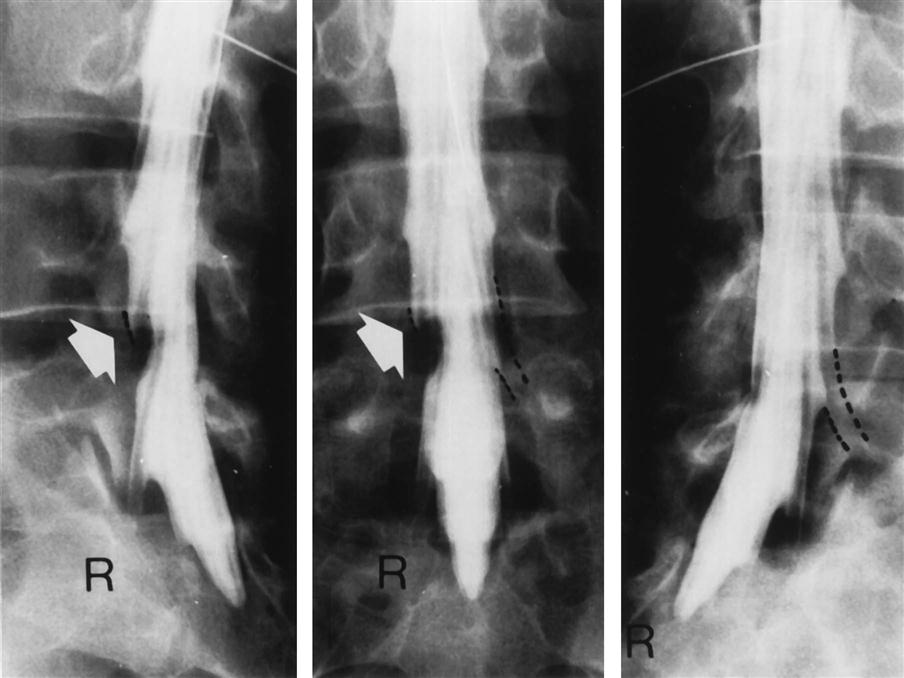

A myelogram, although seldom used today because of its complications and replacement by computed tomography (CT) scans and magnetic resonance imaging (MRI), can confirm the presence of a protruding intervertebral disc, osteophytes, a tumor, or spinal stenosis (Figures 9-113 through 9-115). The examiner must be careful of the side effects of myelograms, which include headache, stiffness, low back pain, cramps, and paresthesia in the lower limbs. Although side effects do occur, no permanent injuries have been noted.